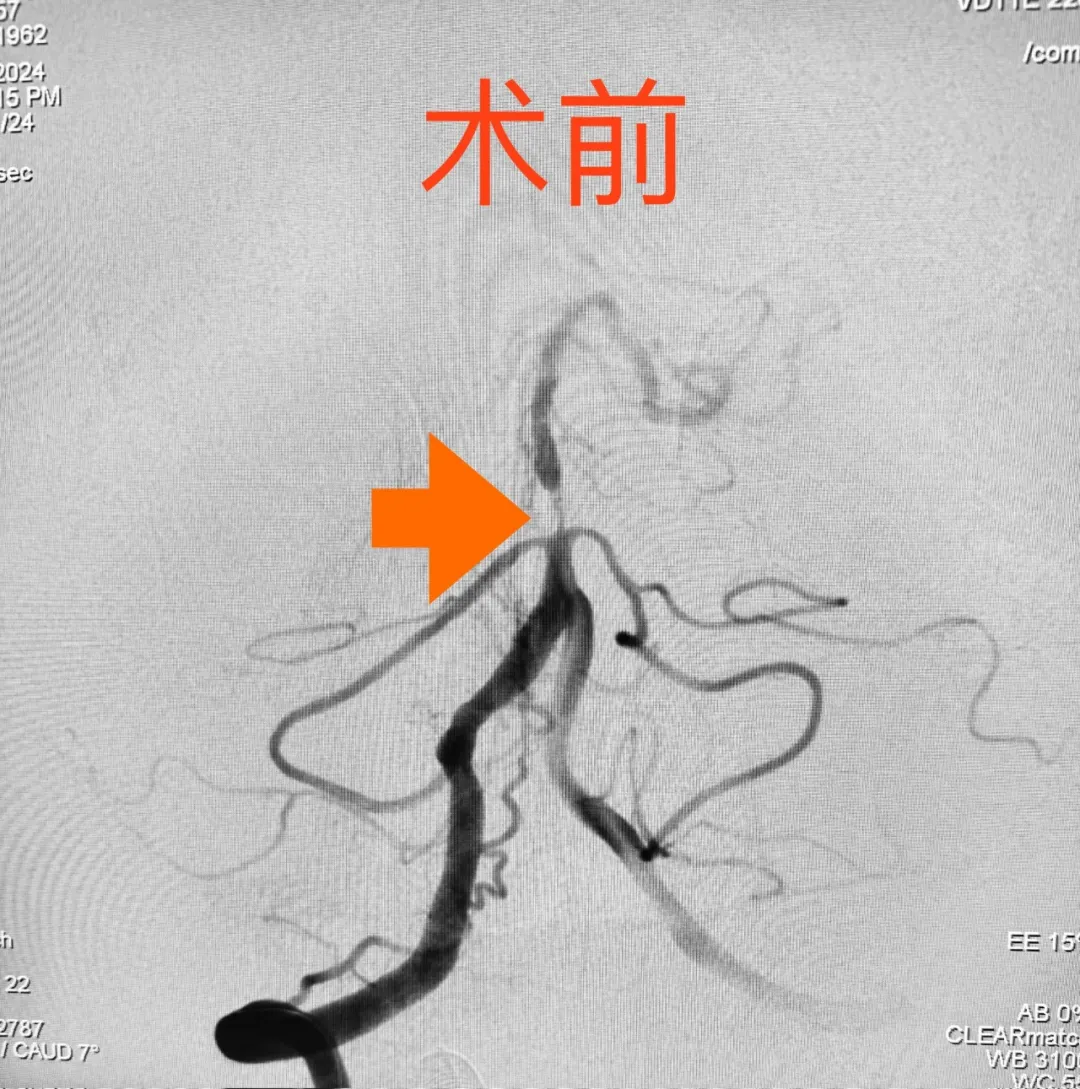

61岁的王大爷最近出现右侧肢体及头面部麻木,且反复发作,每次持续约15分钟,发作时伴有严重头晕、站立不稳,在多家医院检查、治疗,效果就是不好,医院给出的结论是基底动脉重度狭窄、高血压病,不解决血管狭窄问题,头晕恐怕一时半会儿好不了!经过多方打听、朋友介绍,患者来到了长沙经开医院,就诊神经内科主任高小平教授门诊,高主任看了相关医院的检查结果,确诊为“基底动脉中下段极重度狭窄”,狭窄率大约在90%左右,这导致该患者内科药物治疗效果不好的主要原因。为慎重行事,高主任第一时间把患者收住院,次日通过全脑血管造影检查发现,患者的基底动脉中下段严重狭窄,狭窄率在90%以上,左侧颈内动脉C6段中度狭窄;同期行头部磁共振检查,患者有脑干梗死;基于王大爷目前的状况及前一段时间保守治疗效果不佳的情况,科室大讨论后一致认为,患者需尽早进行介入手术干预,如不及时手术,很可能再次脑干梗死,严重时可能危及生命。

我们知道,基底动脉是脑内最重要的血管之一,解除狭窄的手术风险很大,操作具一定难度且对术者有技术要求,同时对术者的心理素质考验也极大;手术时一旦出现斑块脱落、动脉夹层等情况,有可能造成致命的后果。面对这样的手术,面对患者及家属对医院及医生期许的眼光,医生没有选择退缩,而是顶着压力,迎难而上。经过与家属充分沟通后,高小平主任团队凭借丰富的临床经验和反复研究的手术操作流程,决定为患者实施手术治疗——椎基底动脉球囊扩张/支架成形术。

为保证治疗效果,同时减轻患者经济负担,减少手术费用,尽可能地做到不放支架,实现“有介入、无植入”的理想境界,在麻醉科、手术室、介入导管室的共同协作下,手术如所有人期待的那样非常顺利,通过精准定位锁定病变血管狭窄处,实施单纯球囊扩张,扩张后造影显示,狭窄段血管管径恢复满意,血流得到明显改善,手术后麻醉苏醒快;术后,患者头晕症状明显缓解,行走自如,该患者血管狭窄的改善也大大降低了脑梗死再次复发的风险。